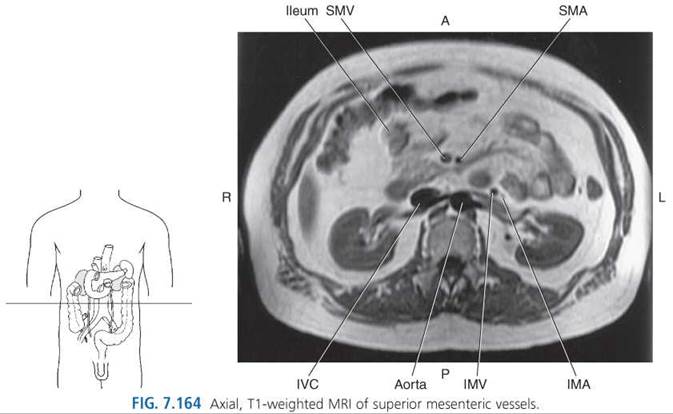

Superior Mesenteric Artery. The large superior mesenteric artery (SMA) emerges just below the celiac trunk at approximately the level of L1 (Figs. 7.139, 7.162, and 7.163). It descends behind the body of the pancreas, then over the horizontal portion of the duodenum to course in the mesentery to the ileum (Figs. 7.158, 7.162, and 7.164-7.167). The artery supplies the head of the pancreas and the majority of the small and large intestines. Branches of the superior mesenteric artery include the inferior pancreaticoduodenal artery, jejunal arteries, ileal arteries, middle colic artery, right colic artery, and ileocolic artery.

The inferior pancreaticoduodenal artery extends to the head of the pancreas and duodenum, and then divides into the posterior ramus, which anastomoses with the posterior superior pancreaticoduodenal artery, and the anterior ramus, which anastomoses with the anterior superior pancreaticoduodenal artery. The jejunal and ileal arteries extend to supply the jejunum and ileum, except the end segment near the cecum. The middle colic artery reaches the transverse colon, and the right colic artery passes to the ascending colon. The ileocolic artery courses behind the peritoneum across the right ureter into the right iliac fossa and divides to supply a portion of the ascending colon, cecum, vermiform appendix, and terminal portion of the ileum (Figs. 7.166 and 7.168).

Inferior Mesenteric Artery. The inferior mesenteric artery (IMA) arises 3 to 4 cm above the bifurcation of the aorta at approximately the level of L3-L4. It descends in front of the abdominal aorta and then to the left, where it gives off the left colic artery, sigmoid arteries, and the superior rectal artery (Figs. 7.164, 7.165, and 7.169). The left colic artery is a retroperitoneal structure that passes along the anterior surface of the left psoas and quadratus lumborum muscles. It bifurcates into ascending and descending branches that supply the walls of the left third of the transverse colon and the entire descending colon. The sigmoid branches (2 or 3) course within the mesentery to supply branches to the terminal descending colon and to the sigmoid colon. The superior rectal artery crosses the common iliac artery and vein as it descends to branch and supply the rectum (Figs. 7.169-7.171).